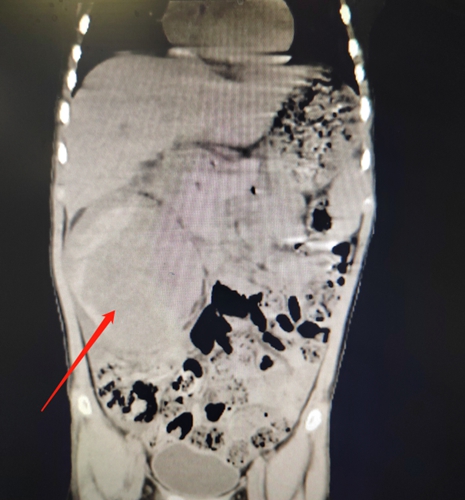

一份CT檢查報告引起了兒童腫瘤外科接診醫(yī)生的注意:映入眼簾的是右側(cè)腎區(qū)一枚巨大的腫瘤,腫瘤來源于右側(cè)腎臟,右側(cè)腎臟幾乎已經(jīng)看不到正常的腎臟組織了!

此時,這個3歲多的小男孩眼瞼及面部已有水腫,結(jié)膜及口唇蒼白。血常規(guī)顯示血紅蛋白只有90g/L!兒童腫瘤外科專家立刻判斷患兒患有右側(cè)腎母細胞瘤合并有腫瘤瘤內(nèi)出血。

待患兒生命體征平穩(wěn)后,團隊對其進行了右側(cè)腎臟腎母細胞瘤的根治手術(shù)。術(shù)中,手術(shù)團隊發(fā)現(xiàn)腫瘤已膨脹到將升結(jié)腸及橫結(jié)腸推移到了左側(cè)腹。同時,升結(jié)腸及其系膜與腫瘤粘連緊密,腫瘤內(nèi)側(cè)壁與十二指腸粘連緊密,并且緊貼下腔靜脈。腫瘤瘤體內(nèi)有出血,腫瘤張力極大,稍有不慎,極可能引起腫瘤供應(yīng)血管破裂,引發(fā)大出血,大大增加了手術(shù)難度。

手術(shù)團隊沉著冷靜、仔細操作,電刀逐步凝切腫物,結(jié)扎血管……最終,歷時2個多小時,手術(shù)順利完成。腫瘤無破裂且被完整切除,腫瘤有12*9*7cm大小。經(jīng)過細心護理,目前童童已康復(fù)出院。